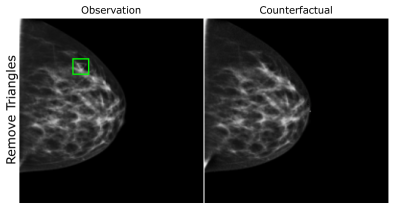

EMBED

Using prior insights, we apply our mechanisms to a real-world artefact removal task on the EMory BrEast imaging Dataset (EMBED) (Jeong et al., 2022). Schueppert et al. (2024) observe that triangular and circular skin markers are spuriously associated with breast cancer in classifiers due to shortcut learning (Geirhos et al., 2020), and manually labelled 22,012 affected mammograms. Using this dataset, we train a significantly scaled-up, amortised, anti-causally guided semantic mechanism () to remove skin markers. We model triangular markers (), circular markers (), breast density (), and cancer () as independent parents of the mammogram , and remove artefacts by intervening on and while holding and fixed. Figure 6 shows that our mechanisms effectively remove artefacts and can disentangle representations for triangles and circles. We successfully remove of triangles and of circles in our test set - a noteworthy result given the dataset’s small size and the scarcity of labelled skin markers (Appendix I).